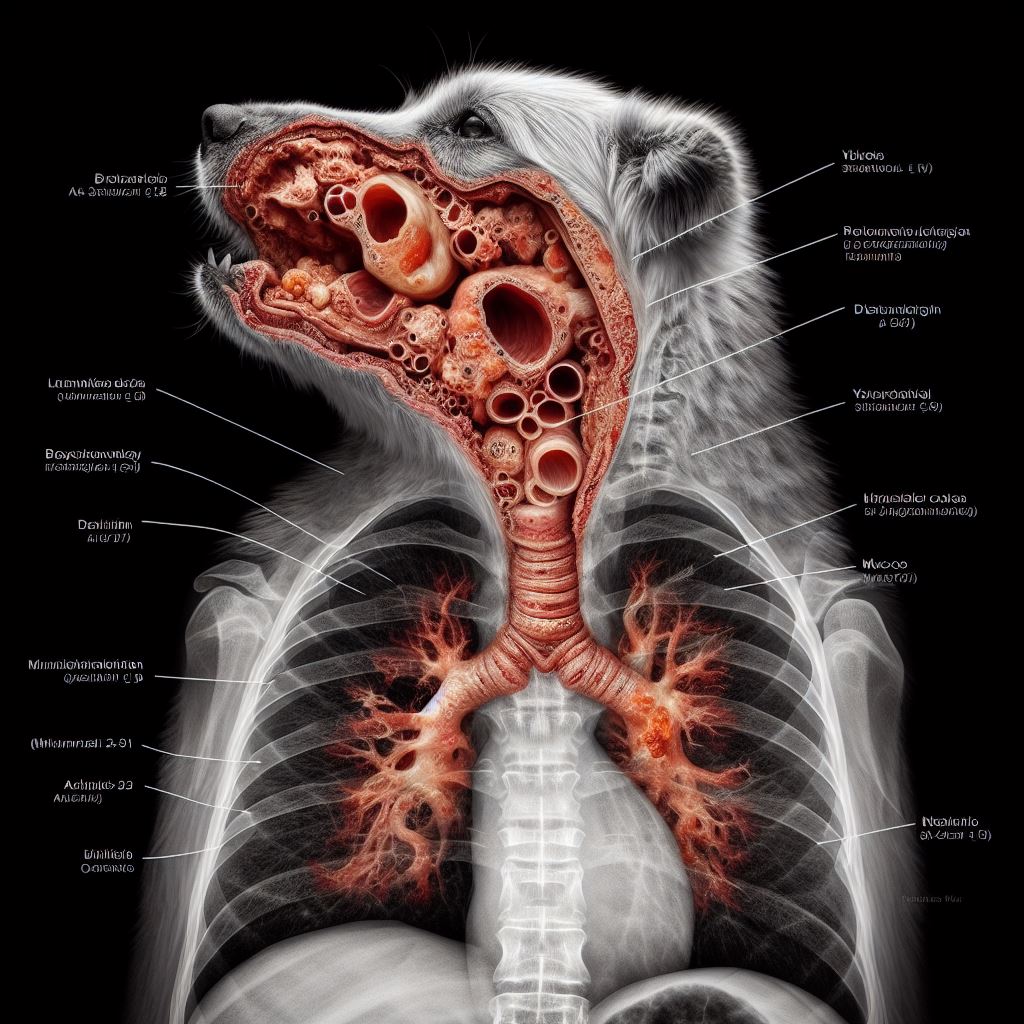

강아지 기관지 협착증 원인과 증상, 치료 방법 알아보기 사진

강아지 기관지 협착증 치료 방법

약물 치료

강아지 기관지 협착증의 치료에는 약물 치료가 일반적으로 사용됩니다. 의사의 처방에 따라 기관지 확장제 및 소염제를 투여하여 증상을 완화시키는데 도움을 줍니다. 기관지 확장제는 기관지를 더 넓게 열어 호흡 과정에서 공기의 흐름을 원활하게 만들어 줍니다. 소염제는 기관지의 염증을 줄여주어 호흡에 어려움을 줄이는 역할을 합니다.

비약물 치료

약물 치료 외에도 허브 치료나 천연 요법을 활용한 비약물 치료가 고려될 수 있습니다. 이러한 치료법은 약물 치료에 부작용이나 의존성을 우려하는 경우에 선택할 수 있는 대안입니다. 허브 치료는 특정 허브나 식물 추출물을 사용하여 염증을 감소시키거나 호흡 기관을 진정시키는데 도움을 줍니다. 천연 요법은 건강에 좋은 식단, 영양 보충제, 생활 습관의 개선 등을 통해 증상 을 예방하고 증상을 완화시키는데 도움을 줍니다.

수술적 치료

심각한 경우에는 수술이 필요할 수 있습니다. 수술적 치료는 기관지 협착증을 완전히 치료하는 가장 효과적인 방법 중 하나입니다. 이는 의사와의 상담을 통해 결정되어야 하며, 기관지를 넓게 열어주거나 기관지의 퇴행을 막는 등 다양한 수술 방법이 있습니다. 수술적 치료는 일부 강아지에게는 필요한 선택일 수 있으나, 수술은 항상 리스크와 부작용을 동반할 수 있으므로 신중하게 결정해야 합니다.